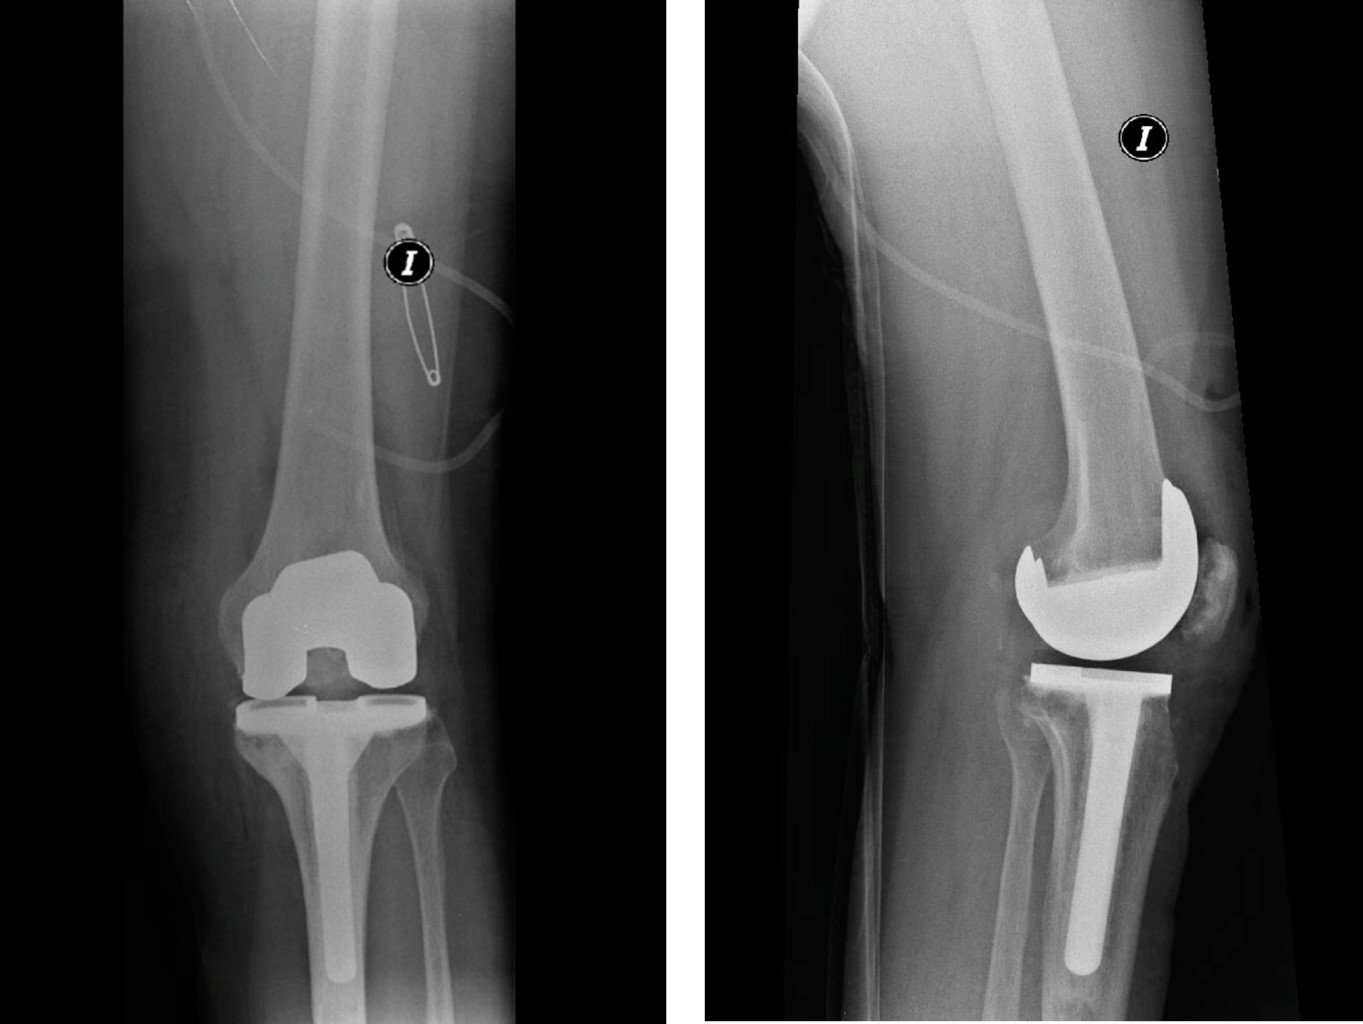

Figure 5

Figure 6